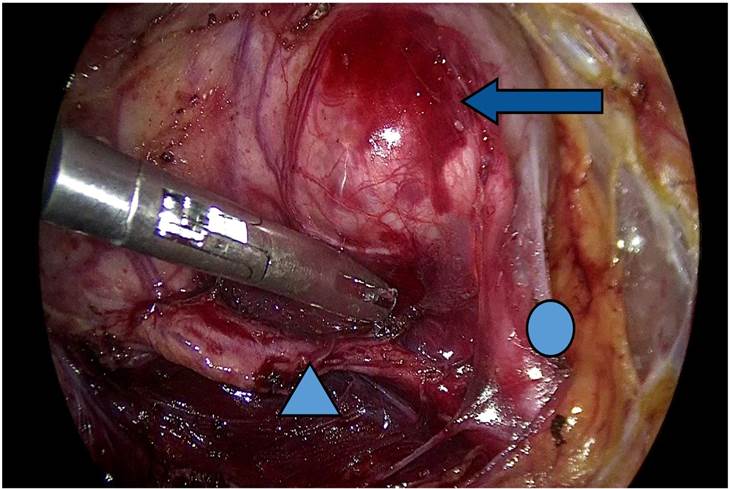

Se realiza acceso con técnica de tres puertos. Con dos puertos de 10 mm, el tercero de 5 mm, por abordaje transperitoneal, se accedió a espació retroperitoneal hasta localizar unidad renal, donde se observó aumento de volumen en polo inferior. Al realizar disección de la cápsula renal, llama la atención la presencia de aumento de volumen en polo inferior con salida de aparente uréter con implantación en tercio superior del segundo sistema colector de polo superior. Se realiza disección hasta poder exponer en totalidad polo inferior renal, y se realiza punción con aguja laparoscópica obteniendo orina con abundante detritus, se drena hasta colapsar aparente pelvis, y se realiza ligadura de sistema colector por encima de la implantación y destechamiento de sistema colector, se procede a revisión de hemostasia y colocación de drenaje pasivo tipo Penrose (Imágenes 4, 5, 6, 7, 8 a 9).

Flecha: polo renal inferior (aparente quiste), circulo: Sistema Colector Inferior, triangulo: Sistema Colector Superior.

Imagen 4 Imágenes de la cirugía laparoscópica con técnica transperitoneal